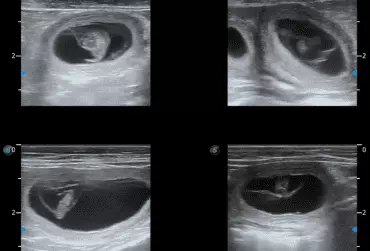

W literaturze opisano niewiele przypadków ciąż bliźniaczych jednokosmówkowych u suk. W trakcie wczesnej diagnostyki ultrasonograficznej ciąży u suki rasy whippet (chart angielski) zobrazowano pęcherz ciążowy, w którym znajdowały się dwa zarodki. Podczas badań kontrol­nych zarodki, a później płody wykazywały prawidłową organogenezę i żywotność. Ich rozwój przebiegał podobnie względem pozostałych ośmiu płodów. W 63. dniu ciąży wykonano zabieg cesarskiego cięcia i wydobyto dwa płody tej samej płci, o bardzo podobnym wyglądzie, z dwóch pęcherzy płodowych przyczepionych do jednego łożyska, oraz pozostałe osiem płodów.